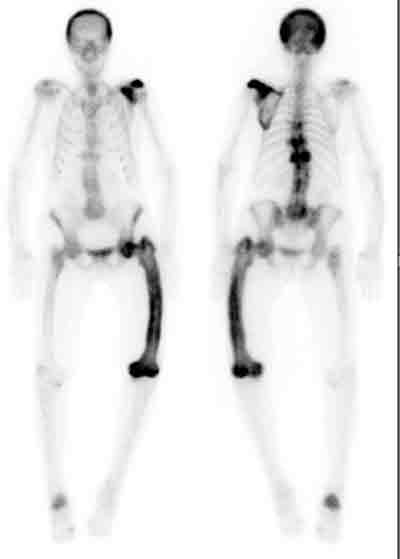

Paget’s disease is diagnosed primarily by radiological examination. Early in the course of the disease, lytic activity predominates, causing focal osteolytic lesions (osteoporosis circumscripta) or flame-shaped, advancing lytic wedges in the long bones (Box 2A). Subsequently, areas of sclerosis develop, leading to the characteristic appearances of mixed lytic and sclerotic areas, thickened trabeculae, bone expansion, cortical thickening and deformity. The radiological appearances are usually characteristic, but occasionally a differential diagnosis of sclerotic or lytic metastases needs to be considered. An isotope bone scan is recommended in all patients as part of the initial diagnostic assessment to determine the distribution of the disease, in particular the involvement of sites with the potential for complications, such as base of skull, spine and long bones (Box 3). Computed tomography scanning is helpful to assess skull-base involvement (including patients with deafness), spinal stenosis or other neurological complication.